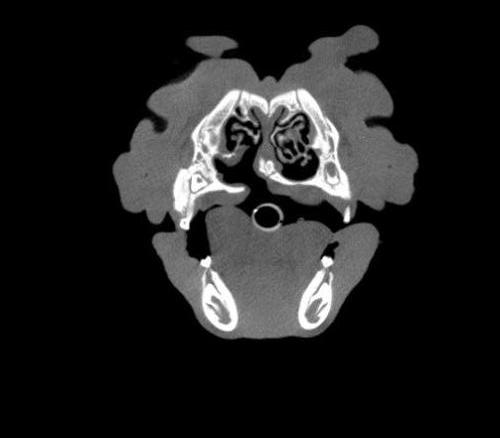

The Center now provides advanced imaging via cone beam CT. Cone beam CT is excellent for visualization of bony structures of the skull, nasal cavity, teeth, and ears. Cone beam CT is especially helpful for diagnosing dental disease and evaluation of jaw fractures. It can also be useful for evaluating the sinuses and tympanic bulla. Cone beam CT can be used in conjunction with nasal biopsy and culture to evaluate nasal discharge whether chronic or acute.

Some animals are born with a defect in their mouth called a cleft palate. These animals may have chronic upper respiratory infections and nasal discharge. They are also at risk for developing aspiration pneumonia. While repair of some of these defects may be difficult, there are multiple techniques available for repairing or reducing the size of the defects. We also repair acquired defects that resulted from the loss of teeth, trauma, or failure to heal after oral surgery.

In addition to dentistry and oral surgery procedures we also offer advanced surgical procedures for diseases of the head and neck. With Dr. Kendall Taney’s advanced training in oral and maxillofacial surgery, we are able to provide treatments for a variety of diseases such as chronic ear infections, tumors of the head and neck, and nasal/sinus issues.